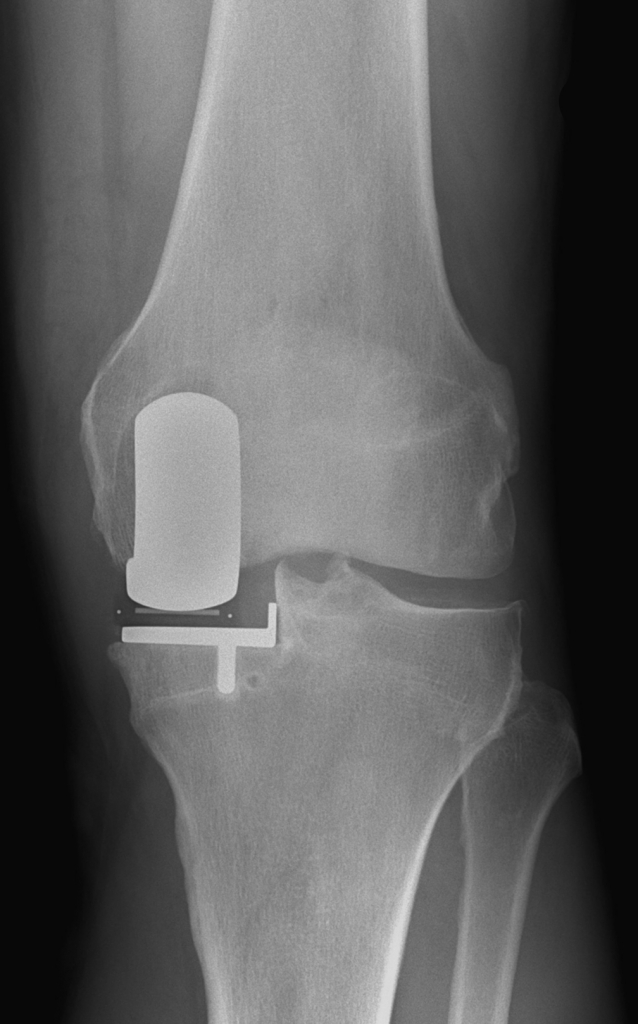

Die Hemischlittenprothese (Teilgelenkersatz) ist eine gute Möglichkeit, das eigene Kniegelenk nur teilweise zu ersetzen und damit das restliche Kniegelenk so lange wie möglich zu erhalten. Die Operationszeit und damit das Risiko von Komplikationen ist im Vergleich zur Vollprothese vermindert, gleichzeitig ist der Heilungsverlauf wesentlich verkürzt und die allgemeine Zufriedenheit nach Gelenkersatz erhöht. Die Langzeitergebnisse entsprechen nahezu denen einer Vollprothese, weshalb ein Teilgelenkersatz auf jeden Fall in Betracht gezogen werden sollte.

Die Hemischlittenprothese (oder Halbschlittenprothese) wird bei einseitiger Abnützung des Kniegelenkes auf der Innen- oder Aussenseite des Kniegelenkes eingesetzt. Kontraindikationen für die Implantation eines Halbschlittens sind die Arthrose des kontralateralen Kompartimentes, die rheumatoide Arthritis, eine Varus-Valgusdeformität von mehr 10°, ein Streckdefizit von mehr als 10° und die Kreuzbandinsuffizienz, insbesondere für die mobilen Gleitlager (erhöhte Luxationsgefahr).